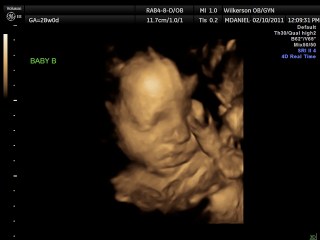

We had our 4-D ultrasound today. James would not cooperate at all but Jackson did. He was so precious he kept his hand over his face though. It was so neat. They are definitely cramped in there. We go back Monday and hopefully James will work with us. Here our a few pictures we have more but they are video rather than pictures.

Here is sweet Jackson: